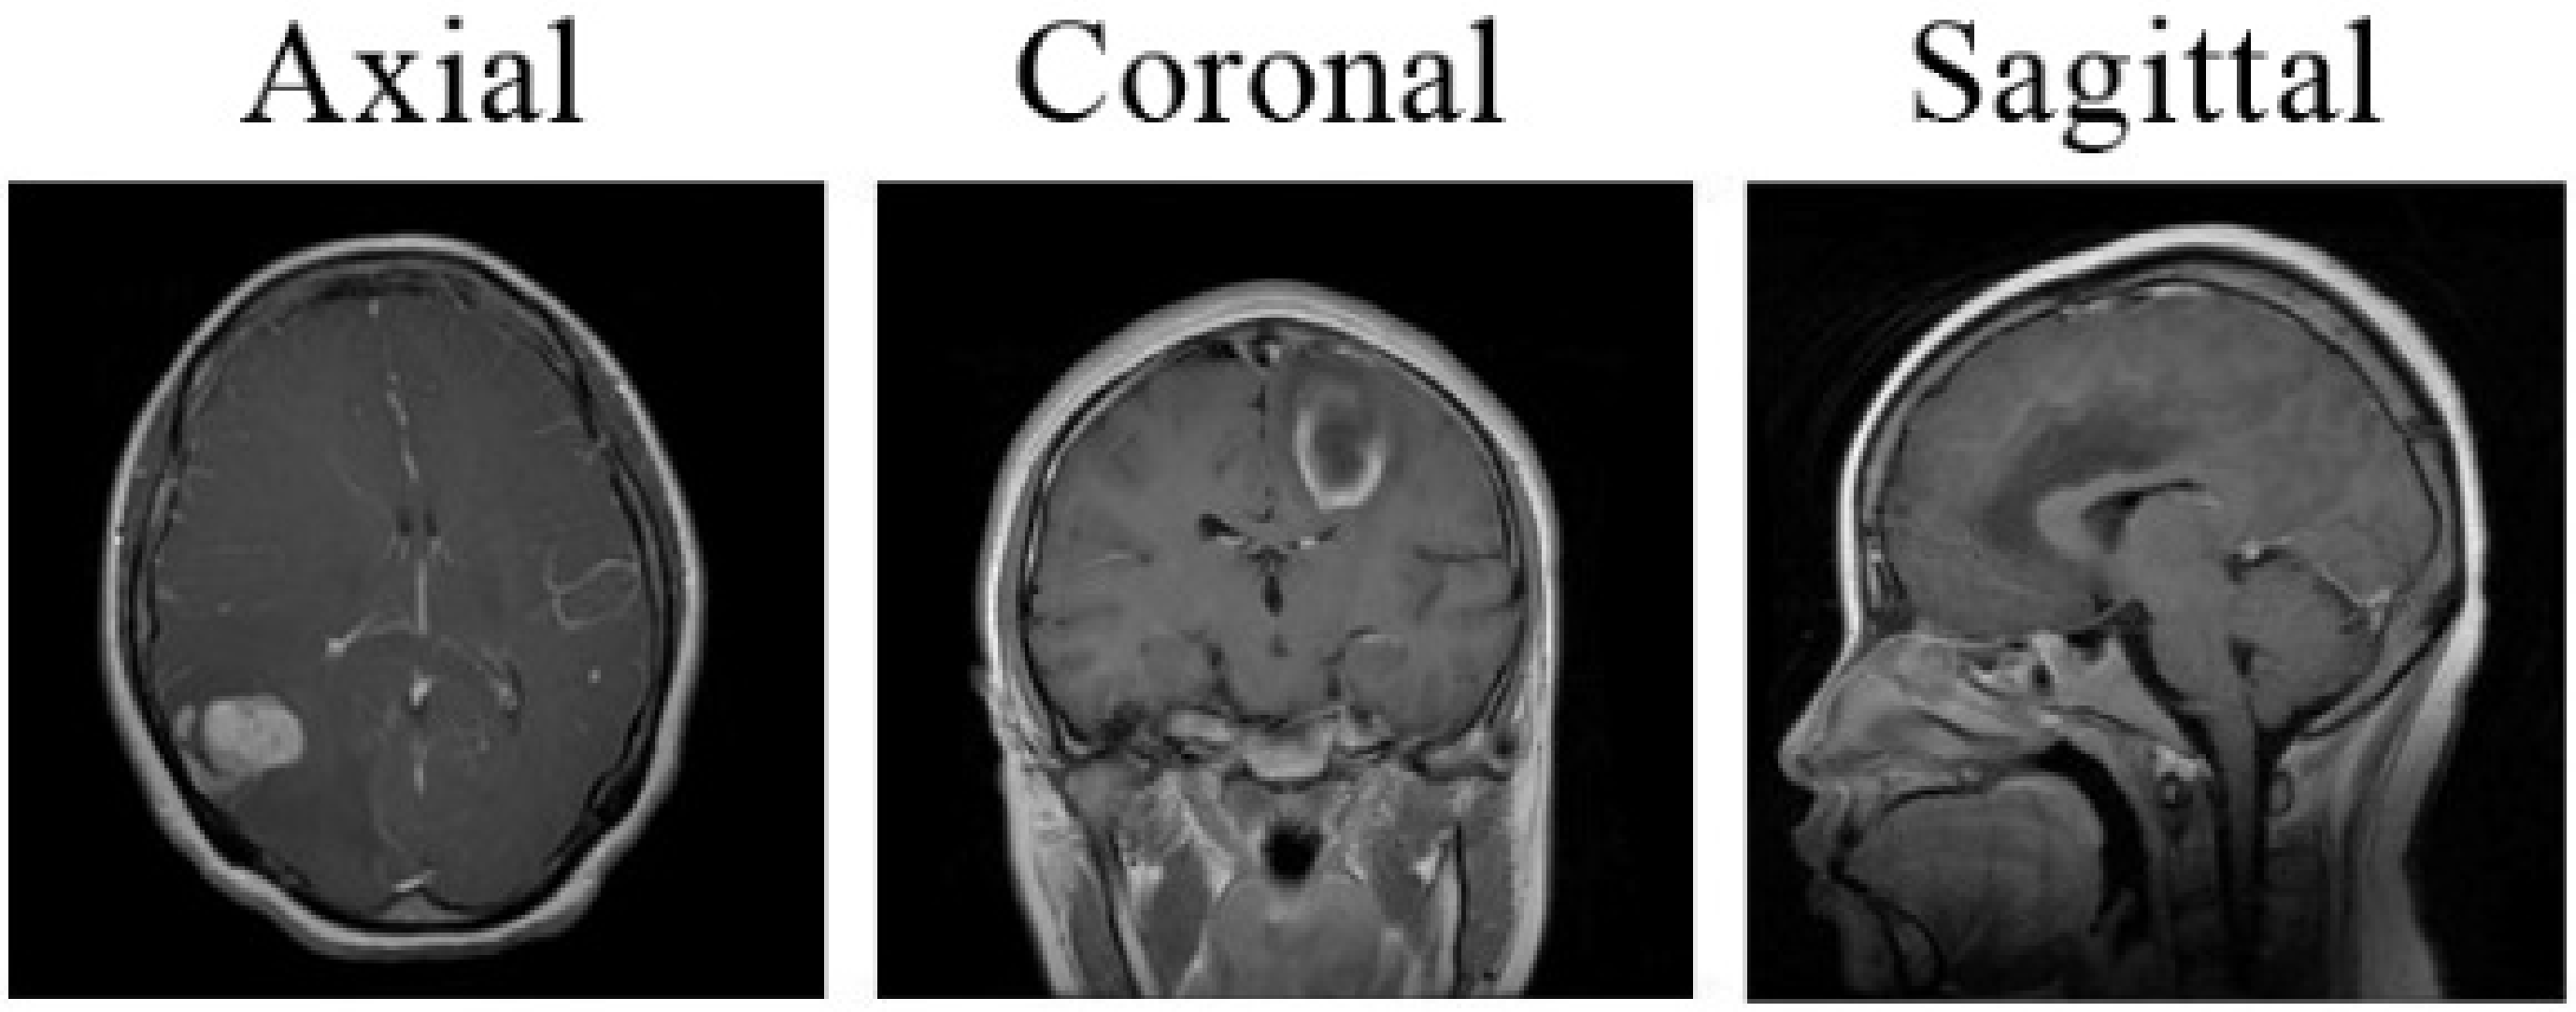

3.1. Dataset and Preprocessing